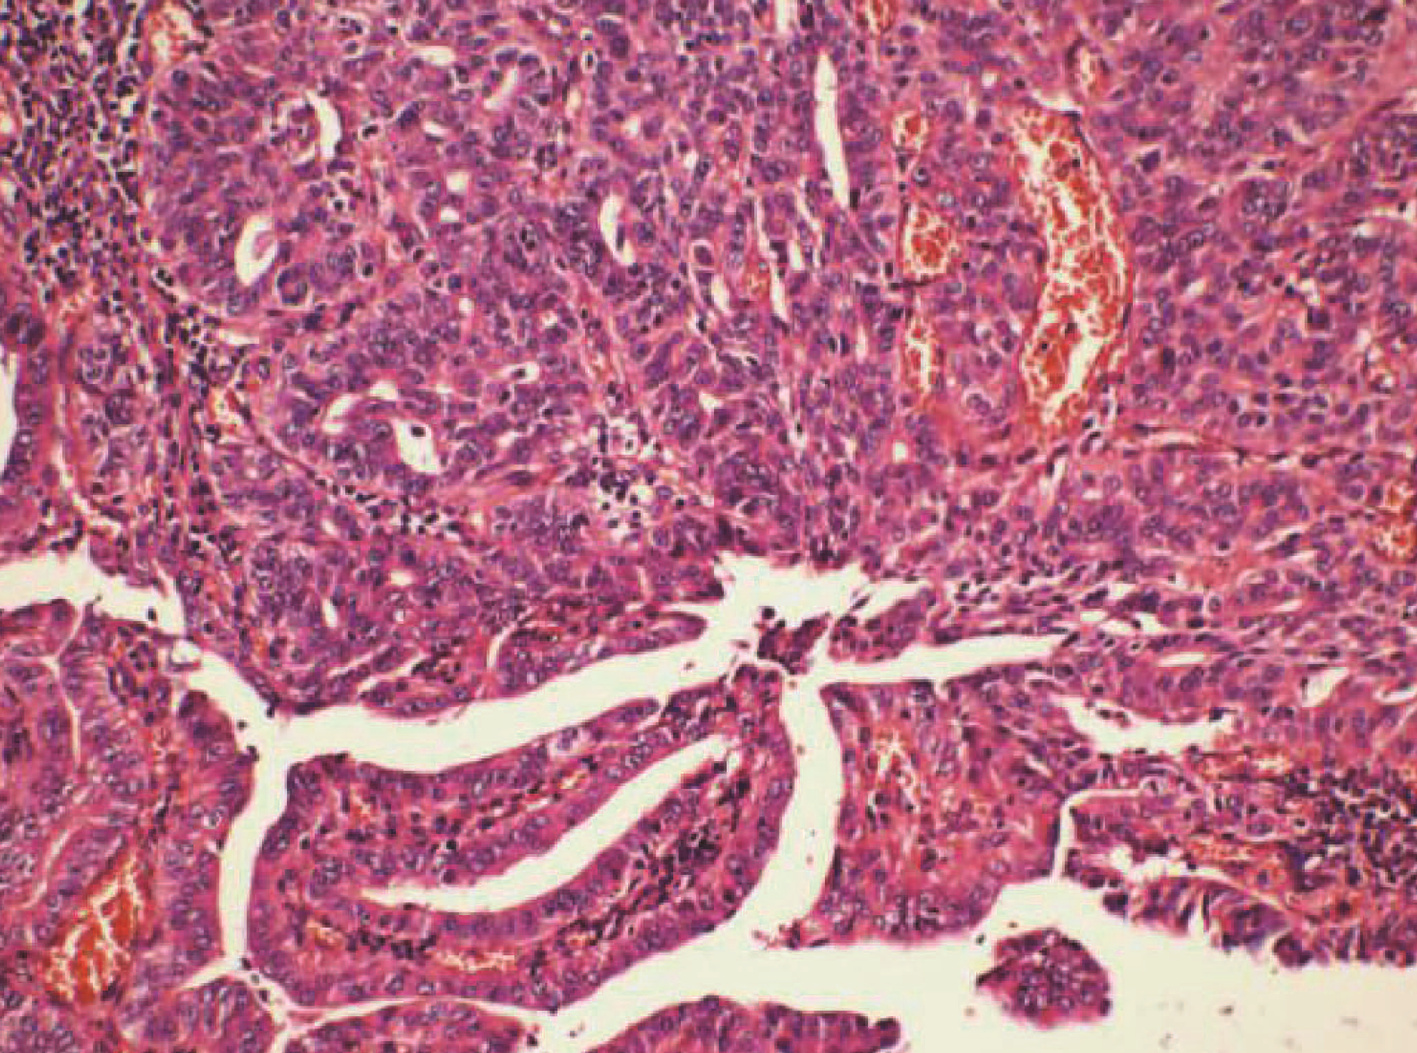

摘要(924) HTML (473) PDF (2302KB)(74)

摘要: